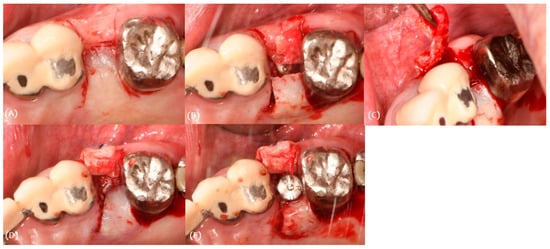

3.2. Case 2

3.3. Case 3